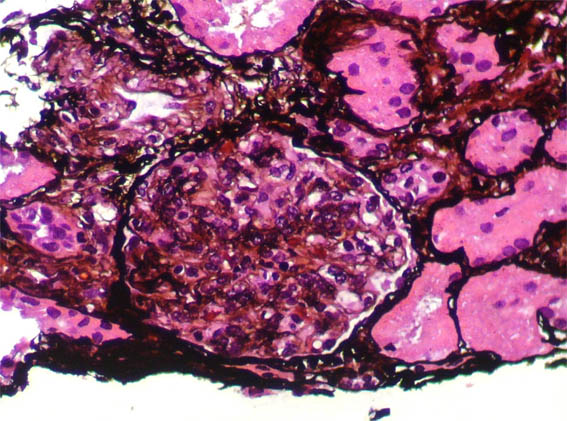

Figura 7.

Plata-metenamina, X400.